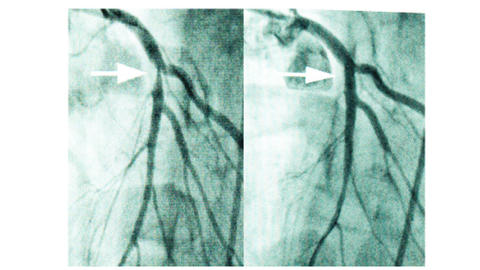

verengte Herzkranzgefäße

© herzemdizin.berlin (links) Herzkranzgefäß mit einer Engstelle (Stenose). (rechts) Nach Beseitigung der Stenose mit einem Ballonkatheter.

Hier kommt die zweite Stärke der Methode zum Tragen. Entdecken Ärztinnen und Ärzte in den Herzkranzgefäßen eine bedeutsame Engstelle (Stenose) oder behandeln sie Patientinnen und Patienten im akuten Herzinfarkt, versuchen sie, Koronararterien wieder durchgängig zu machen. Die Technik heißt perkutane transluminale koronare Angioplastie (PTCA) oder percutaneous coronary intervention (PCI). Was ist darunter zu verstehen? Über den Katheter lassen sich nicht nur Engstellen der Herzkranzgefäße bildlich darstellen, sondern auch öffnen. Dazu schiebt man in vielen Fällen zunächst einen Druckdraht in das verengte Kranzgefäß, der ggf. eine noch präzisere Bestimmung der Engstelle ermöglicht (Druckdrahtmessung; FFR, IFR, RFR). Im Falle einer nachgewiesen bedeutsamen Stenose kann über den Draht ein Ballon bis an die Engstelle vorgebracht und mit hohem Druck entfaltet werden. So wird die Verengung erweitert und ein verbesserter Blutfluss erzeugt. Hier macht man sich die Elastizität der Gefäße zu Nutze: Ablagerungen werden vom Ballon in die Gefäßwand gedrückt. Um in diesem Bereich eine erneute Verengung zu verhindern, setzen Ärztinnen und Ärzte während derselben Untersuchung kleine metallnetzartige Gefäßstützen in das Blutgefäß ein. Diese sogenannten „Stents“ sind heute ganz überwiegend beschichtet und setzen Medikamente frei, damit der behandelte Bereich nicht wieder zuwächst. Gefäßstützen, die vom Körper nach einiger Zeit abgebaut werden, haben bis heute keine überzeugenden Langzeitergebnisse gezeigt. Welche Stents sich eignen und welche gerinnungshemmenden Arzneistoffe (sogenannte Plättchenhemmer) anschließend wie lange erforderlich sind, entscheidet die Ärztin oder der Arzt. Grundsätzlich erfolgt eine PTCA als geplanter Eingriff bei der chronisch stabilen koronaren Herzkrankheit, aber auch als lebensrettender Notfalleingriff beim akuten Herzinfarkt.